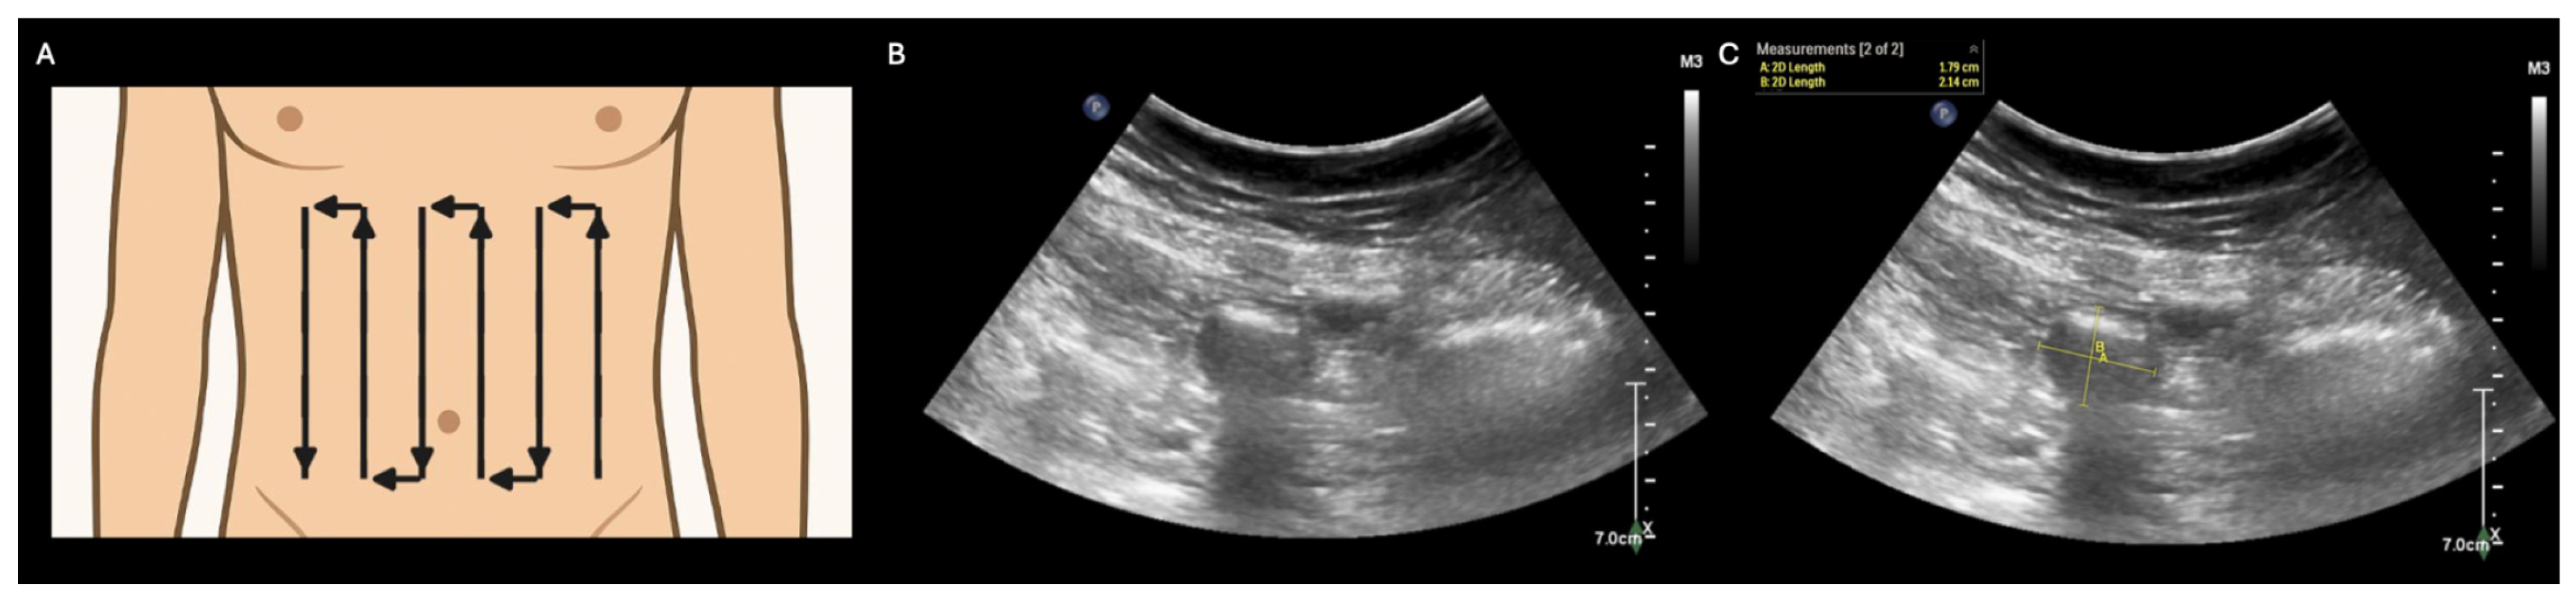

- Abramson, L.; Olive, J.K.; Lefler, B.; Wu, L.; Bowman, A.; Simpson, T.; Vatsaas, C.; Yanamadala, M.; Bronshteyn, Y.S. Point-of-care Ultrasound to Screen for Gastrointestinal Dysfunction: Image Acquisition and Interpretation. J. Vis. Exp. 2025, e68603. [Google Scholar] [CrossRef] [PubMed]

- Atkinson, N.S.S.; Bryant, R.V.; Dong, Y.; Maaser, C.; Kucharzik, T.; Maconi, G.; Asthana, A.K.; Blaivas, M.; Goudie, A.; Gilja, O.H.; et al. How to perform gastrointestinal ultrasound: Anatomy and normal findings. World J. Gastroenterol. 2017, 23, 6931–6941. [Google Scholar] [CrossRef] [PubMed]